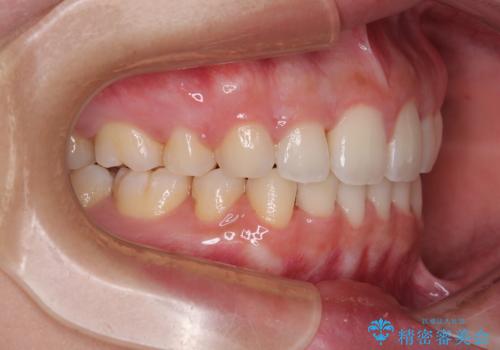

- 全体的なデコボコと口元の突出感を改善したいとのことで来院された患者様です。

このままデコボコを整えるとさらに突出感が増すため、上下左右の第一小臼歯を抜歯し、ワイヤー装置にて矯正しました。

結婚式で途中装置を外した時期がありましたが、2年で治療を終えることができました。